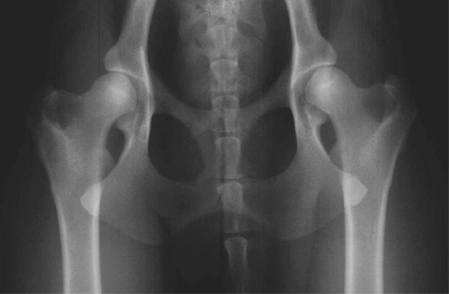

L'esame radiografico viene effettuato sul cane sedato farmacologicamente e mantenuto in decubito dorsale; si richiede una proiezione ventro-dorsale ad arti estesi, mantenuti in adduzione, paralleli alla colonna vertebrale e tra di loro, ruotati internamente e possibilmente paralleli anche al tavolo radiografico, in perfetta simmetria e con sovrapposizione delle rotule alla parte centrale della troclea femorale.

La simmetria viene testimoniata dall'aspetto speculare che devono assumere i fori otturati e i rami e le ali dell'ileo.

Un posizionamento sbagliato , sia per mancanza di simmetria del bacino, sia per adduzione e/o rotazione insufficiente od eccessiva dei femori, pregiudica la possibilità di effettuare una lettura corretta.

Per ottenere un posizionamento adeguato il dorso del cane deve essere contenuto in un apposito sostegno a doccia con gli arti fissati al tavolo radiografico mediante lacci o contenuti manualmente. In caso di posizionamento insoddisfacente l'esame deve essere ripetuto fino a ottenerne uno conforme alle caratteristiche richieste.

In presenza di situazione anatomica che renda impossibile ottenere un posizionamento perfetto, devono essere inviati alla centrale di lettura due o più radiogrammi con il miglior posizionamento ottenuto.